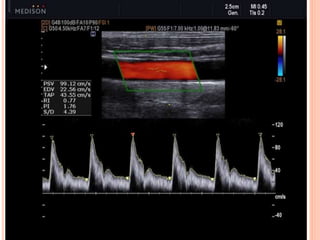

•Spectral Doppler is a method of graphically displaying the

velocity of blood flow through the analysis of frequency and phase shift of

the reflected ultrasound

•Color Doppler visualize the flow or movement of a structure,

typically used to image blood within an artery. Blood flow velocities

increase through a region of narrowing, like a finger pressing up against

the end of a running garden hose. Increased velocities indicate a region of

narrowing or resistance